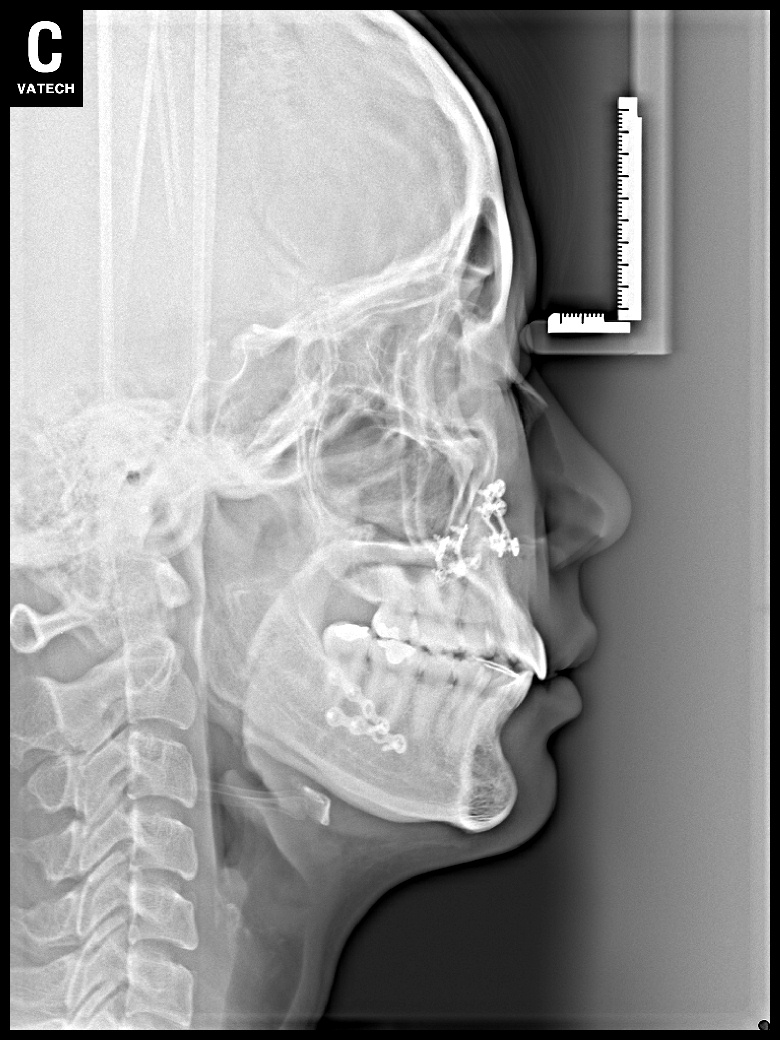

치료 전 사진입니다.